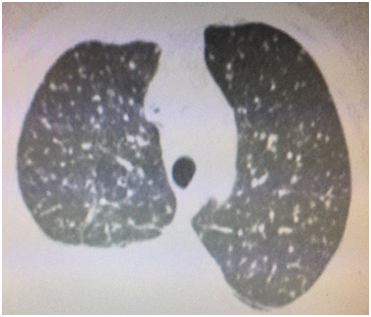

A 57 year old Caucasian female was admitted for dry cough, fever, loss of appetite and chest pain for three weeks. She had a history of tonsillectomy, ankylozing spondylitis, uveitis, pelvis fracture and tibia fracture. Her father died of colonic carcinoma. Her mother had hypertension and previous pulmonary tuberculosis. The patient was under treatment with certolizumab, methotrexate, and prednisolonefor ankylozing spondylitis and uveitis. Daily 300mg isoniazid was also given simultaneously with certolizumab for prophylaxis. Initial laboratory findings revealed WBC 8.2X103/mm3, hemoglobin 10.8g/dl, platelets 341X103mm3, lymphocytes 1.4X103/mm3, creatinine 0.74mg/dl, AST 18IU/L, ALT 18IU/Lmm3, LDH 167IU/L, albumine 3.56gr/dl, CRP 18.6 mg/dl, and calcium 9.1 mg/dl. ECG showed sinus ryhtm. Tuberculin test was negative. Chest x-rayshowed diffuse miliary nodules, alveolar infiltration in the right lower lobe, and right pleural effusion (Figure 1). Pleural protein 4.57g/dl, LDH 353U/L, and albumin 3.56g/dl. Pleural fluid had 1540cells/mm3 with a 74% lymphocyte ratio. Pleural fluid ADA was 114U/L (normal 0-40 U/L). The pleural fluid was exudative compatible with tuberculosis. Computed tomography of the thorax revealed diffuse miliary nodules, infiltration in the right anterior segment of the lower lobe, and right pleural effusion (Figures 2-4). Sputum stains was positive for acid-fast bacilli. Mycobacterium tuberculosis was isolated from the sputum culture. The final diagnosis was miliary tuberculosis associated with certolizumab occuring on the third month of treatment. The patient was commenced on pyrazinamide, isoniazid, rifampicine, and ethambutol treatment for tuberculosis while certolizumab treatment was stopped.

Figure 1 Chest x-ray showing diffuse miliary nodules and right pleural effusion.

The patient had a negative tuberculin test and a normal chest x-ray before certolizumabtreatment. She was commenced on prophylactic isoniazid treatment because the patient had an exposure to active tuberculosis. Miliary tuberculosis with pleural effusion and right lower lobe infiltration occured on the third month of treatment. The patient had an appropriate screening for tuberculosis including medical history, tuberculine test, and chest x-ray before anti-TNF-α treatment was started. The sensitivity of the tuberculine test may have been restricted or diminished by the previous immunosuppressive treatment in our patient. The normal chest x-ray before treatment had also a low diagnostic yield for revealing sequela of past or current infection. Following treatment the right lower anterior segment infiltration was only identified at the computed tomography coronal image and was not detected in chest x-ray.